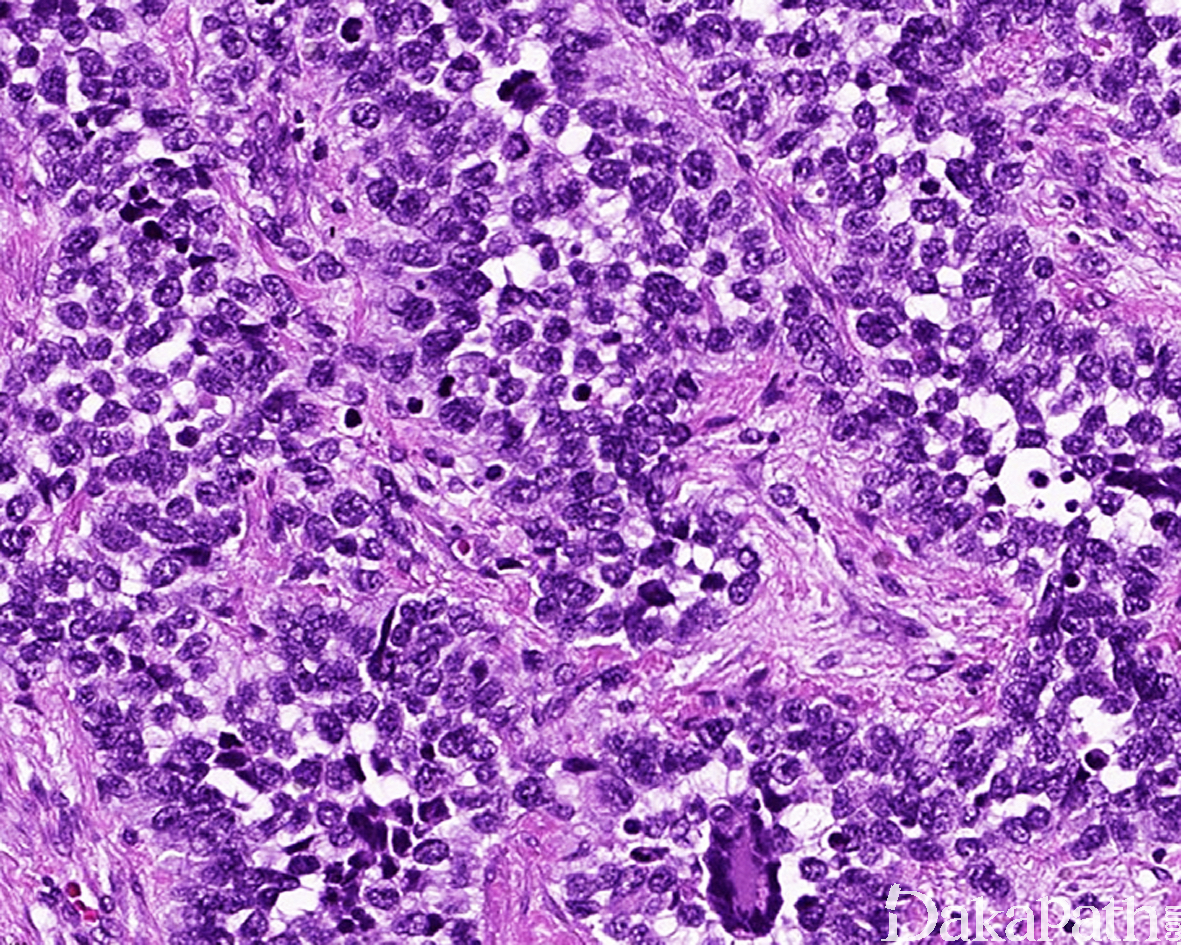

9. 实体型:

10. 由实性的瘤细胞巢组成,瘤细胞圆而较一致,具有纤细的空泡状染色质和小的核仁,部分病例瘤细胞胞质丰富而淡染或透明,类似肾透明细胞癌或软组织透明细胞肉瘤,称透明细胞变型;;

11. 仅偶见或无明显的假腺泡状结构。